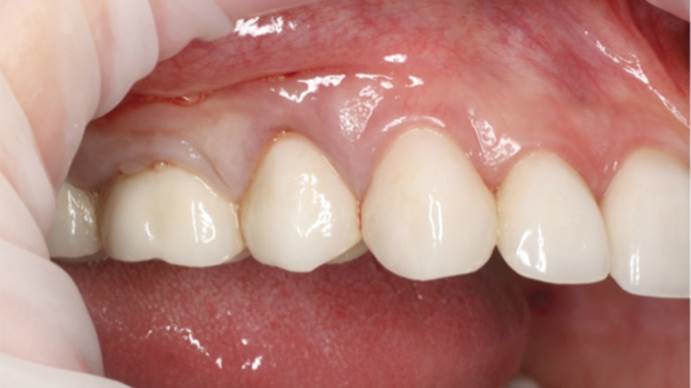

Clinical case: Full-arch implant treatment with immediate loading & extraction implantation

- Courtesy of Dr. Laurent Sers, France -

AnyRidge, R2GATE, guided surgery, Dr. Laurent Sers, immediate loading, maxilla

AnyRidge implant system, R2GATE, Digital prosthesis

“Only AnyRidge has incredible primary stability & good space

for biologic tissues at the most critical part

of the implant, the neck. ”